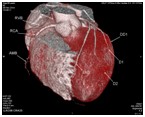

影像科特色检查:心血管CT成像

心脏大血管CT成像

冠状动脉CT成像